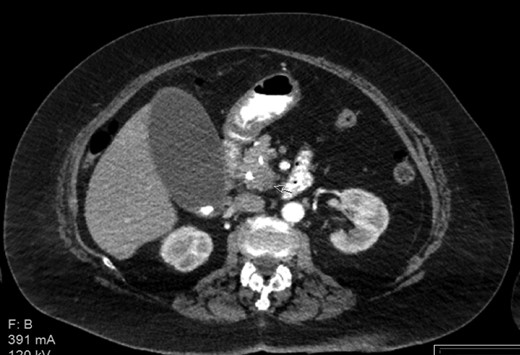

The patient is a 73-year-old elderly Caucasian woman who was initially evaluated for generalized pruritus and painless jaundice for several weeks. Past medical history was significant for Hypertension, and Obesity. Family history and social history was noncontributory. Review of systems was negative except for jaundice and pruritus. Initial laboratory workup revealed WBC 12.0 × 103/ul, Hemoglobin 12.0 g/dl, Platelets 191 × 103/ul. Liver chemistry significant for aspartate aminotransferase (AST) 104 U/l, alanine aminotransferase (ALT) 98 U/l, alkaline phosphatase (ALP) 176 U/l, total bilirubin 5.7 mg/dL and albumin 3.9 g/dL. Carbohydrate antigen 19-9 (CA 19-9) was elevated at 278 u/l. Endoscopic retrograde cholangiopancreatography (ERCP) showed distal common bile duct stricture needing a stent placement. Endoscopic ultrasound (EUS) showed 25 mm diameter pancreatic head mass. Fine needle biopsy of pancreatic head mass was suggestive of adenocarcinoma. MDCT of pancreas (Fig. 1) and liver along with PET /CT scan (Figs 2 and 3) were performed for staging, which were negative for distant metastasis. Patient underwent Whipple’s procedure. Surgical pathology was positive for poorly differentiated pancreatic ductal adenocarcinoma. Lymph nodes involving celiac axis and hepatic artery were negative for malignancy, but 6 out of 28 regional lymph nodes came positive for malignancy on pathology report. Intraoperatively liver parenchyma appeared abnormal and intraoperative ultrasound revealed early fibrosis. Random wedge biopsy from lateral segment of the liver was performed to confirm liver parenchymal disease, which interestingly came positive for 2 mm pancreatic adenocarcinoma metastatic lesion amongst fibrotic liver tissue (Fig. 4). Case was discussed in multidisciplinary conference and referred to oncology for chemotherapy. On 8 months follow up, patient maintained good performance status without any recurrence.

PET/CT scan. Pancreatic head mass with fludeoxyglucose (FDG) uptake.